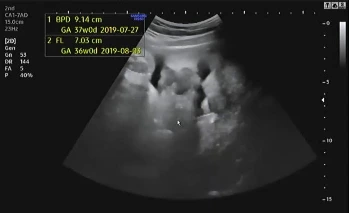

임신 39주 4일 차 병원에 내원해 초음파를 확인했다. 지난번에 이어 큰 이상이 없어 2주 뒤에 내원했는데 다행히 태아도 그동안 건강함을 알려주듯 초음파를 보는 내내 열심히 움직였다.